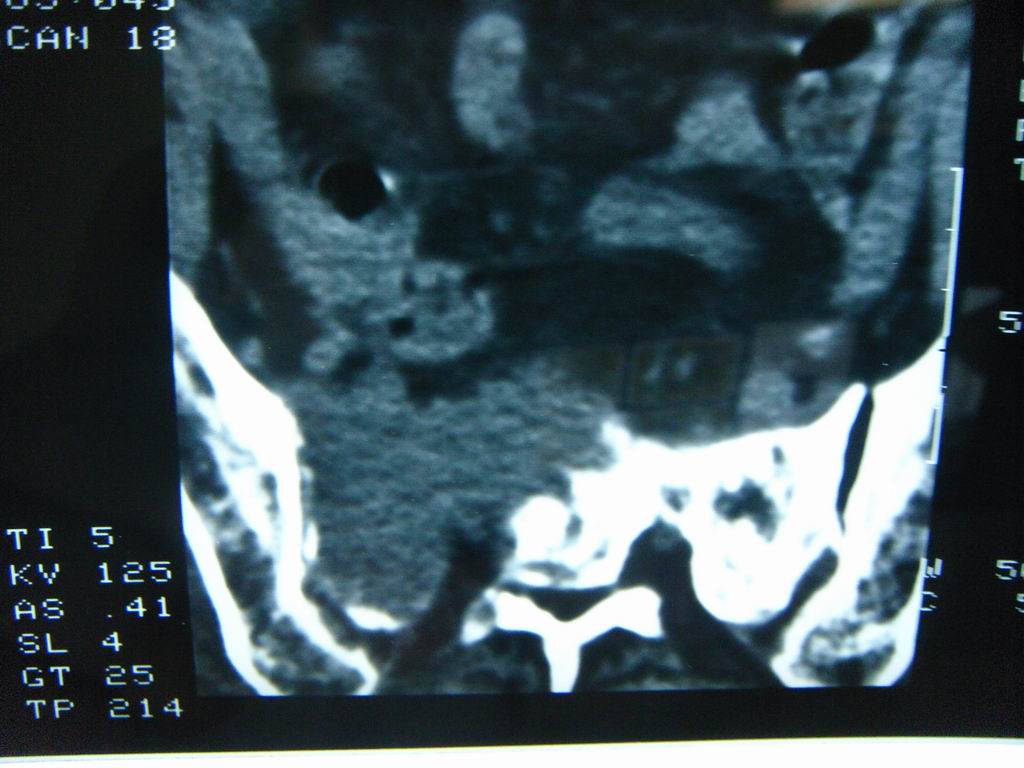

标题: CT21430:女性65岁 乳腺癌术后3年 [打印本页]

标题: CT21430:女性65岁 乳腺癌术后3年

结合病史,考虑骶骨转移瘤,但软组织肿块未突破骨壳,骨巨细胞瘤不能完全排除,骨髓瘤及脊索瘤不考虑。

结合病史,考虑骶骨转移瘤。

结合病史,考虑骶骨转移瘤。其它椎体,如腰5是否有问题呢?

个人感觉骨巨细胞瘤可能性大些。